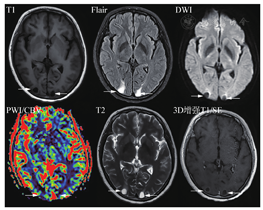

目前使用的MR对比剂均为钆的螯合物。不同厂家造影剂有弛豫率方面的一些差异,但不影响诊断效能。尽管双倍或三倍剂量可以提高病灶显示程度,考虑到钆可能在体内沉积和肾纤维化风险,共识只推荐单倍剂量,但强调在注射造影剂后扫描DSC PWI和T2,然后再扫描增强T1,相当于一定程度的延迟扫描,使病灶显示更明显。

在常规MRI扫描中,最低标准要求在注射造影剂后,插入一个T2序列,即不影响T2图像上病灶的显示,又能获得充分的病灶"强化"时间。优化序列中在注射造影剂后最先行DSC扫描,然后是T2扫描,最后是增强后T1以及后续不同时间的延迟扫描。笔者的实践体会是,首先,增强后短时间内T2图像和平扫T2图像显示的信息一致,不影响诊断;其次,DSC由于分辨率及变形问题,对非实性大病灶提供的增加诊断价值有限(图5);最后,转移瘤在DSC和T2后的增强T1扫描图像上,无论大小,基本都已显示,延迟扫描并不增加影响决策的诊断信息。